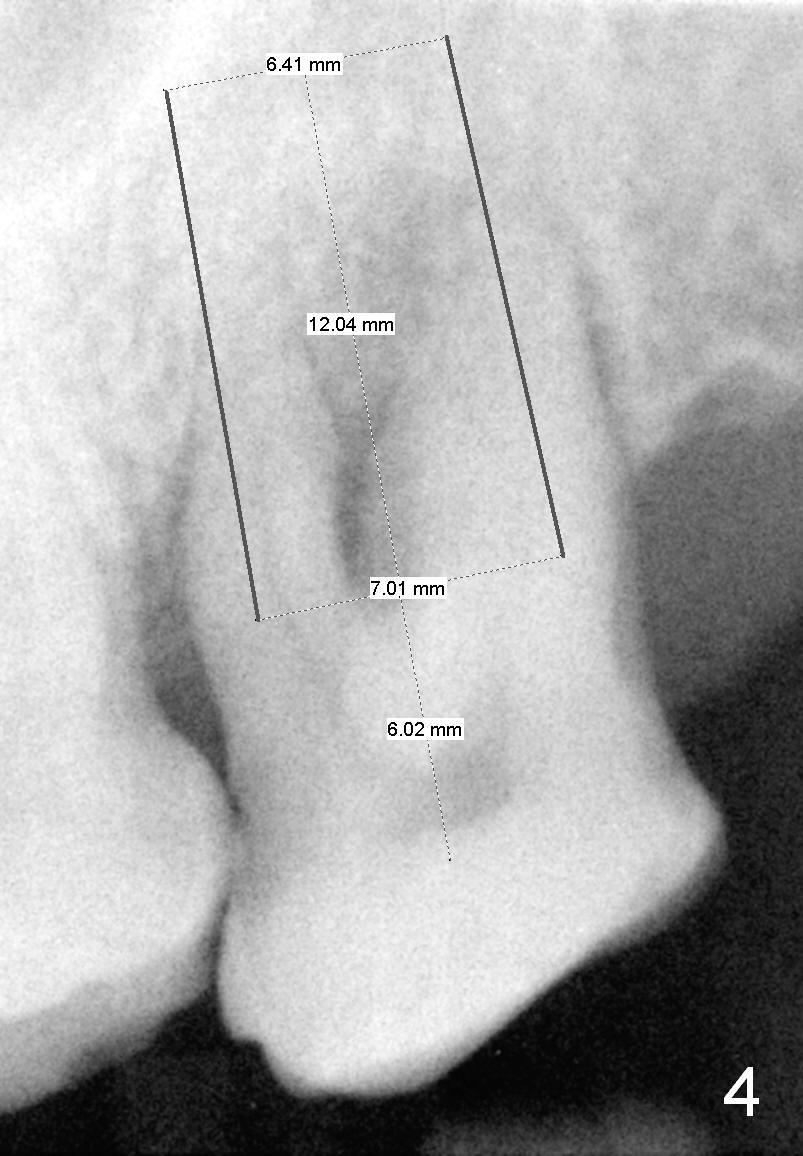

A 53-year-old man (ZB) has history of chronic periodontitis and bruxism. The tooth #18 has been extracted for a few years, while the tooth #15 is going to (Fig.1). Bone height for #15 immediate implant is not a problem (Fig.2-4; green line in Fig.2: sinus floor). After extraction (Fig.5 )socket to be treated with Clindamycin), use starter drill and a 2 mm pilot drill with stopper at 10 mm (Fig.6) on the crest of the septum (Fig.5 S). PA is taken with a parallel pin. Adjust the length accordingly. Subsequent osteotomy will be carried out with drills with stopper at 50 RPM. In brief, the implant does not need to be large. It should be placed as deep as possible (1-2 mm subcrestal mesially and/or distally), since the vertical height in the posterior region is limited. The margin of a cemented abutment is to be slightly subgingival. Use an immediate provisional to close socket gap, while to keep abutment margin from the gingiva. Use Collagen dressing before and after bone graft.